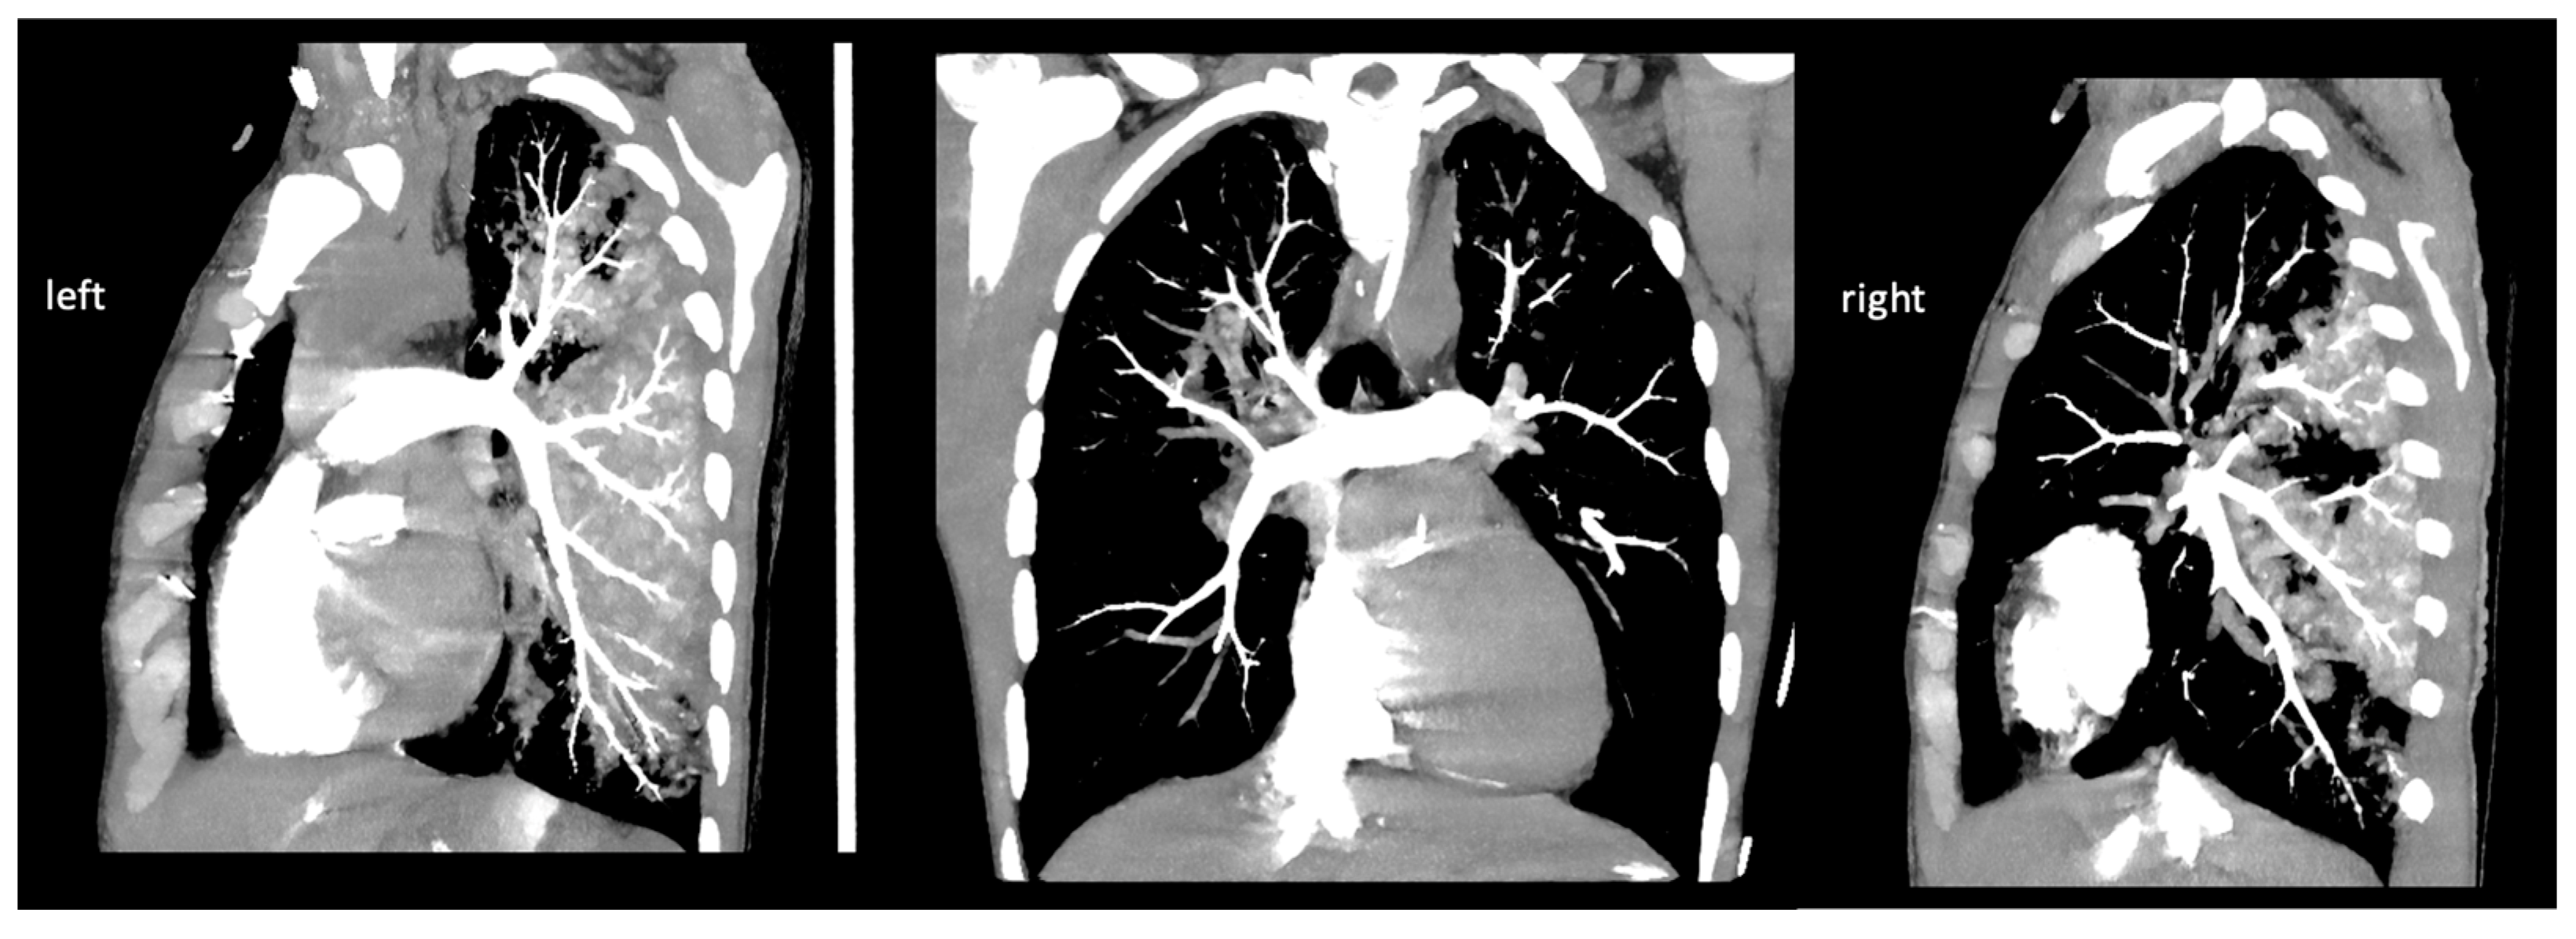

| 21:34 | cranial, thoracic, and abdominal CT scan; pulmonary CT angiography to rule out acute aortic dissection and acute pulmonary embolism | |